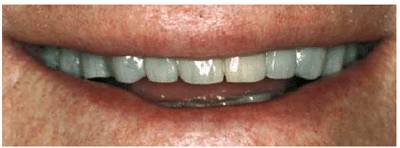

procedure can be seen in Figures 17-8A

and B 17-8C 17-8D 17-8E 17-8F 17-8G 17-8H and I, which show a 45-year-old man with

evidence of gingival and incisal abrasion, erosion, and abfraction. It is

Figure 17-8A and B: This 45-year-old man shows extreme tooth loss due to combination lesions both gingivally and incisally of abrasion, erosion, and abfraction.

Figure 17-8H and I: Although early intervention is the best approach, restoring the defects at any point is both functionally and esthetically beneficial. Bonding is especially effective in preventing further damage to the tooth surface it covers.